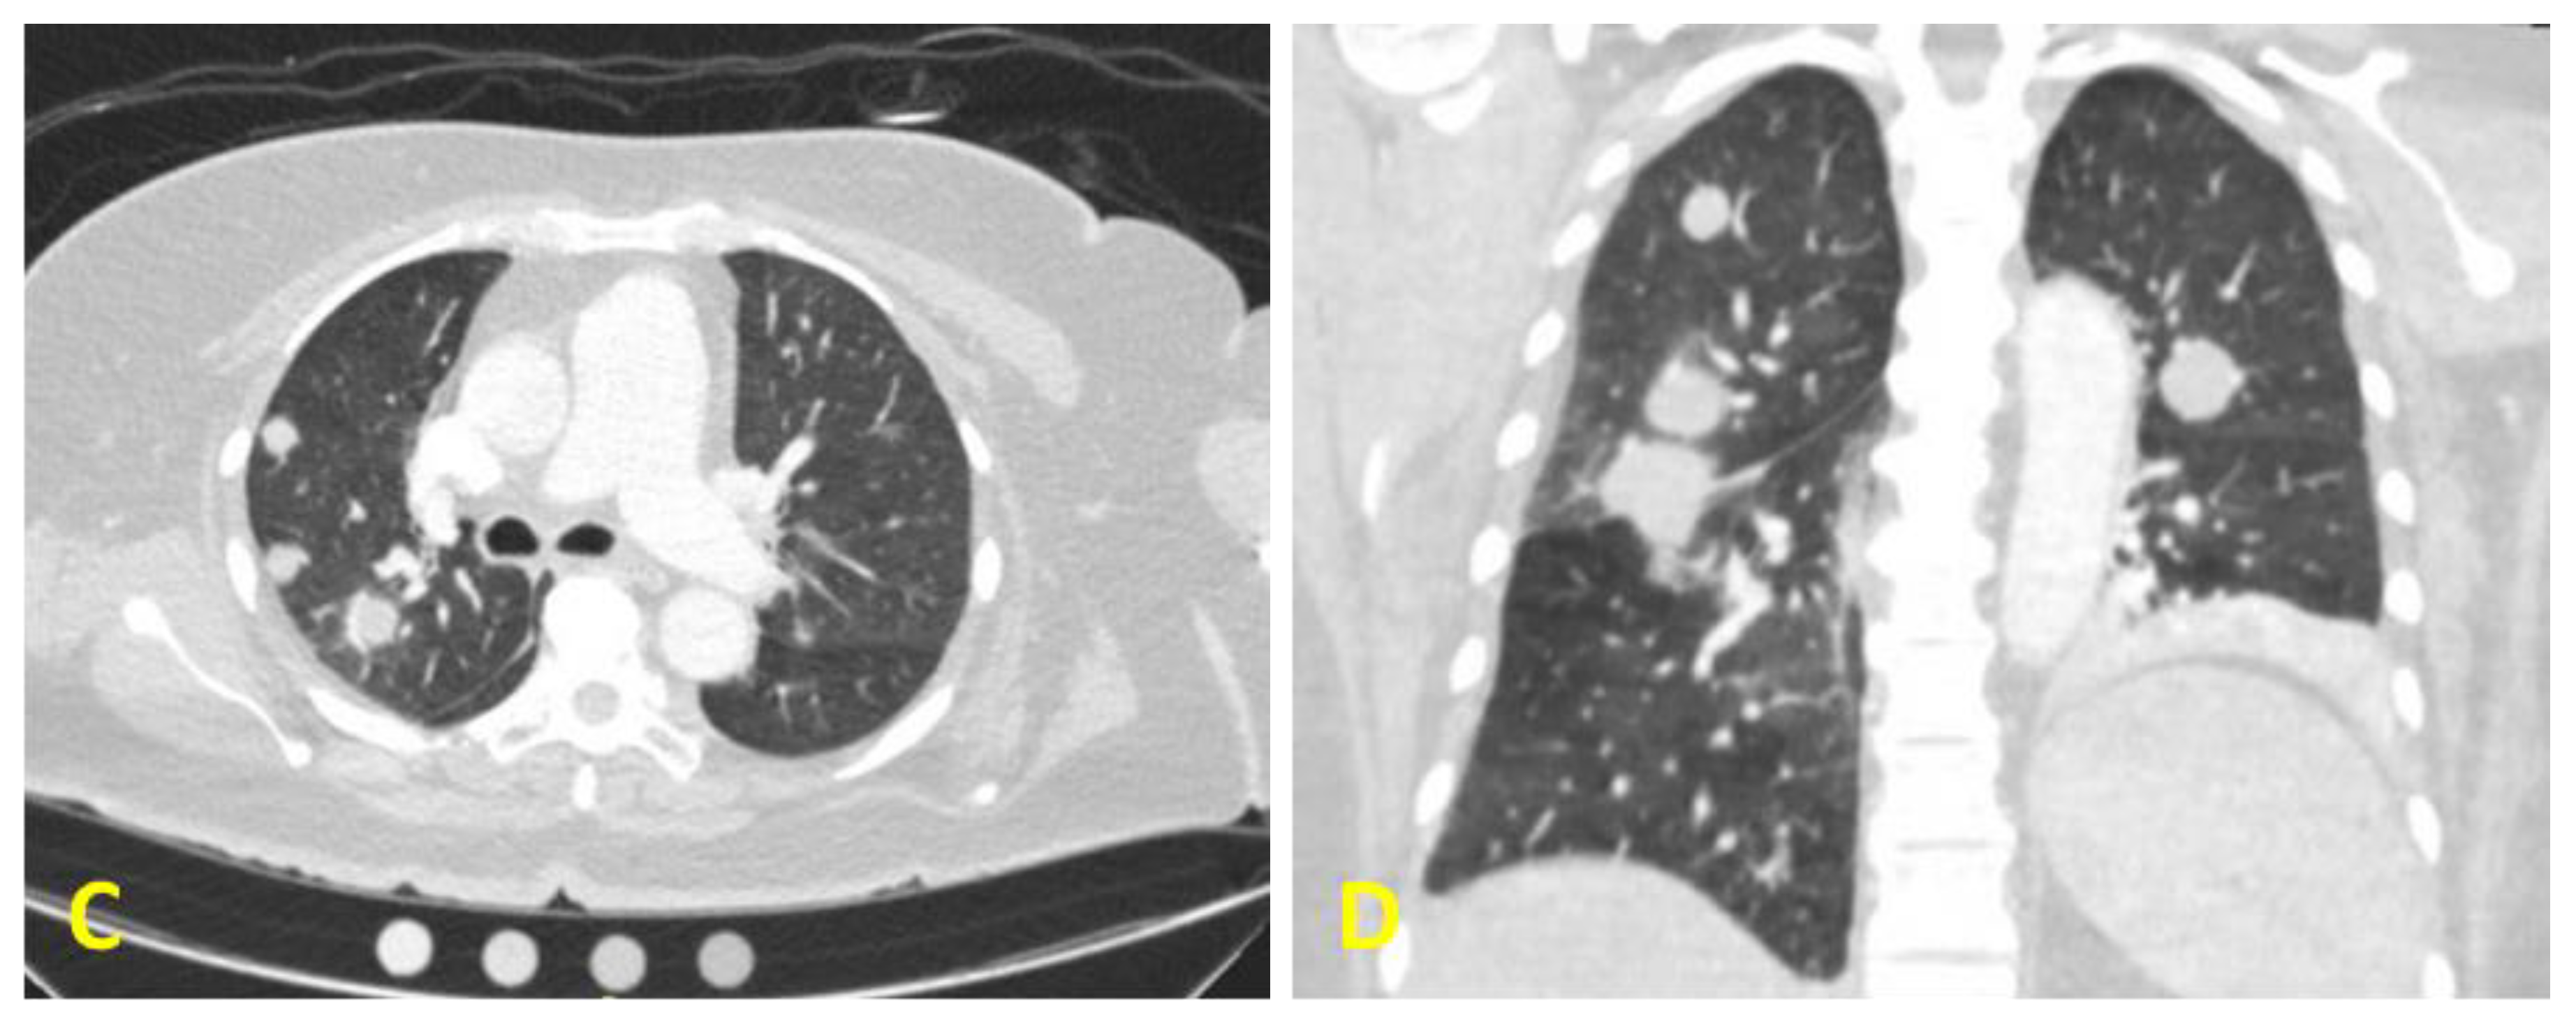

. Pada parenkim paru nodul metastasis soliter dan multipel cenderung didapati pada bagian perifer dan diperkirakan berasal dari penyebaran hematogen. Metastatic Breast Cancer is Constantly Changing Find Out Why Its Important to Act Early. Metastasis Penyebaran Metastasis adalah penanaman tumor yang tidak berhubungan dengan tumor primer.